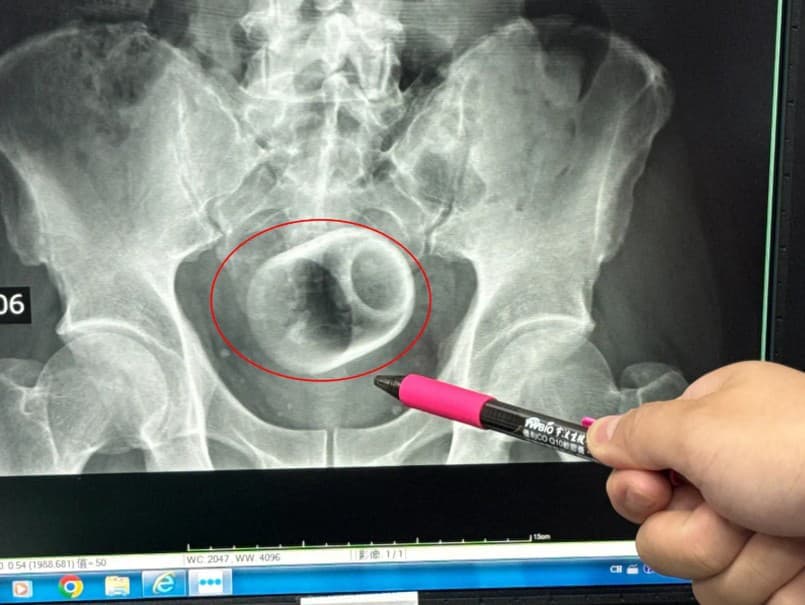

Kuriózny prípad z Taiwanu: Muž s keramickým hrnčekom v tele

Muž z Taiwanu sa dostal do nemocnice s neznesiteľnými bolesťami brucha, pričom lekári objavili nečakaný dôvod jeho ťažkostí. V jeho konečníku sa nachádzal uviaznutý keramický hrnček, čo vyžadovalo núdzovú operáciu.